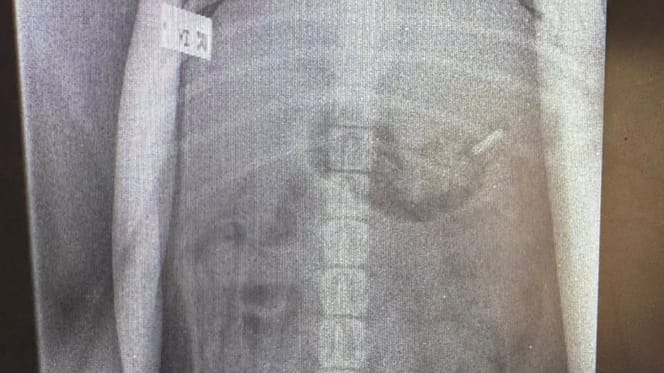

An X-ray of a dog

The vets took an X-ray, which instantly confirmed his owners' fears. Charlie was then rushed into emergency surgery. Fortunately, the operation was a success, and the vet was able to remove the razor blade from the puppy's body without any difficulty.